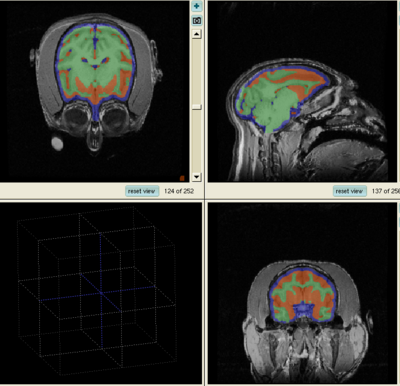

Segmentation Results

1. The results for the best and worst segmentations are shown in the following. For each subject, the first figure shows the alignment of Gray matter atlas (these will be changed to checker board figures aligning target and the whole brain atlas soon) with the brains, and the second figure shows the segmentation results.

Best Segmentation: Oscar